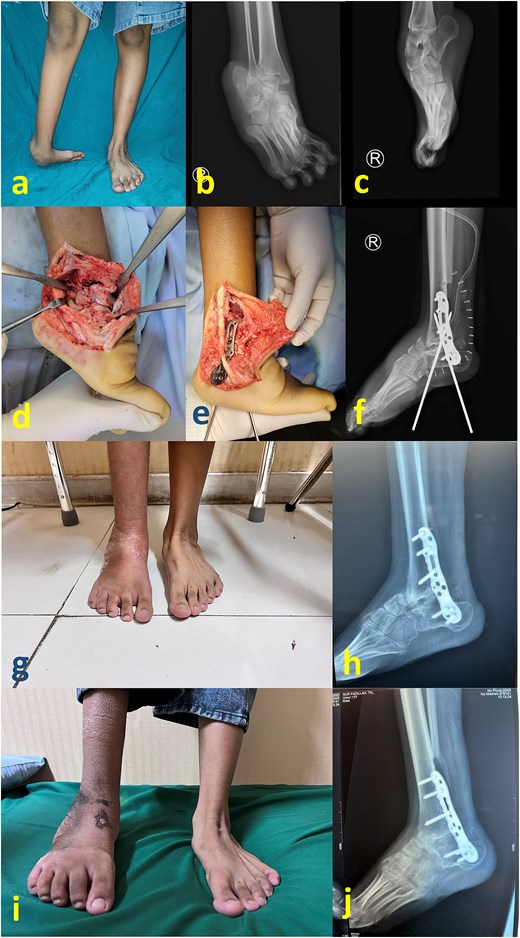

Case 3

A 22-year-old man presented with neglected clubfoot without a prior history of treatment (Fig. 3a–c). The surgical steps were similar to those in Cases 1 and 2 (Fig. 3d and e), except that the fixation was reinforced with merely a posterior cast splint. Postoperative complications occurred, including loss of fixation and wound breakdown (Fig. 3f). A subsequent operation was performed to address this problem, including hardware removal, debridement, and fixation using a ring external fixator (Fig. 3g and h). The external fixator was removed after 2 months (Fig. 3i), and weight bearing was allowed. The wound healed uneventfully, stable and platigrade ankle, as well as the healed arthrodesis can be observed at 1 year since the first surgery (Fig. 3j–l).

(a) Preoperative clinical image; (b) and (c) preoperative radiograph; (d) intraoperative image after partial talectomy; (e) immediate postoperative radiograph; (f) clinical image after 1 month, showing wound breakdown and loss of fixation; (g) clinical images after reoperation consisted of plate removal, debridement, reduction, and fixation with Ilizarov frame; (h) immediate radiograph after second surgery; (i) clinical image after frame removal at 2 months postoperative; (j) latest follow up image showing stable plantigrade ankle despite a persistent bulk at lateral foot; (k) and (l) latest radiograph at 1 year after first surgery, showing healed arthrodesis.